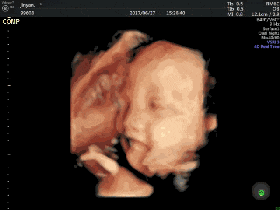

什么是四维彩超?

四维彩超能够表面成像

更加清晰的筛查胎儿的四肢发育是否畸形

是否脑膜膨出,是否唇腭裂

是否脊柱裂等先天畸形

及早发现并及早做出解决方案